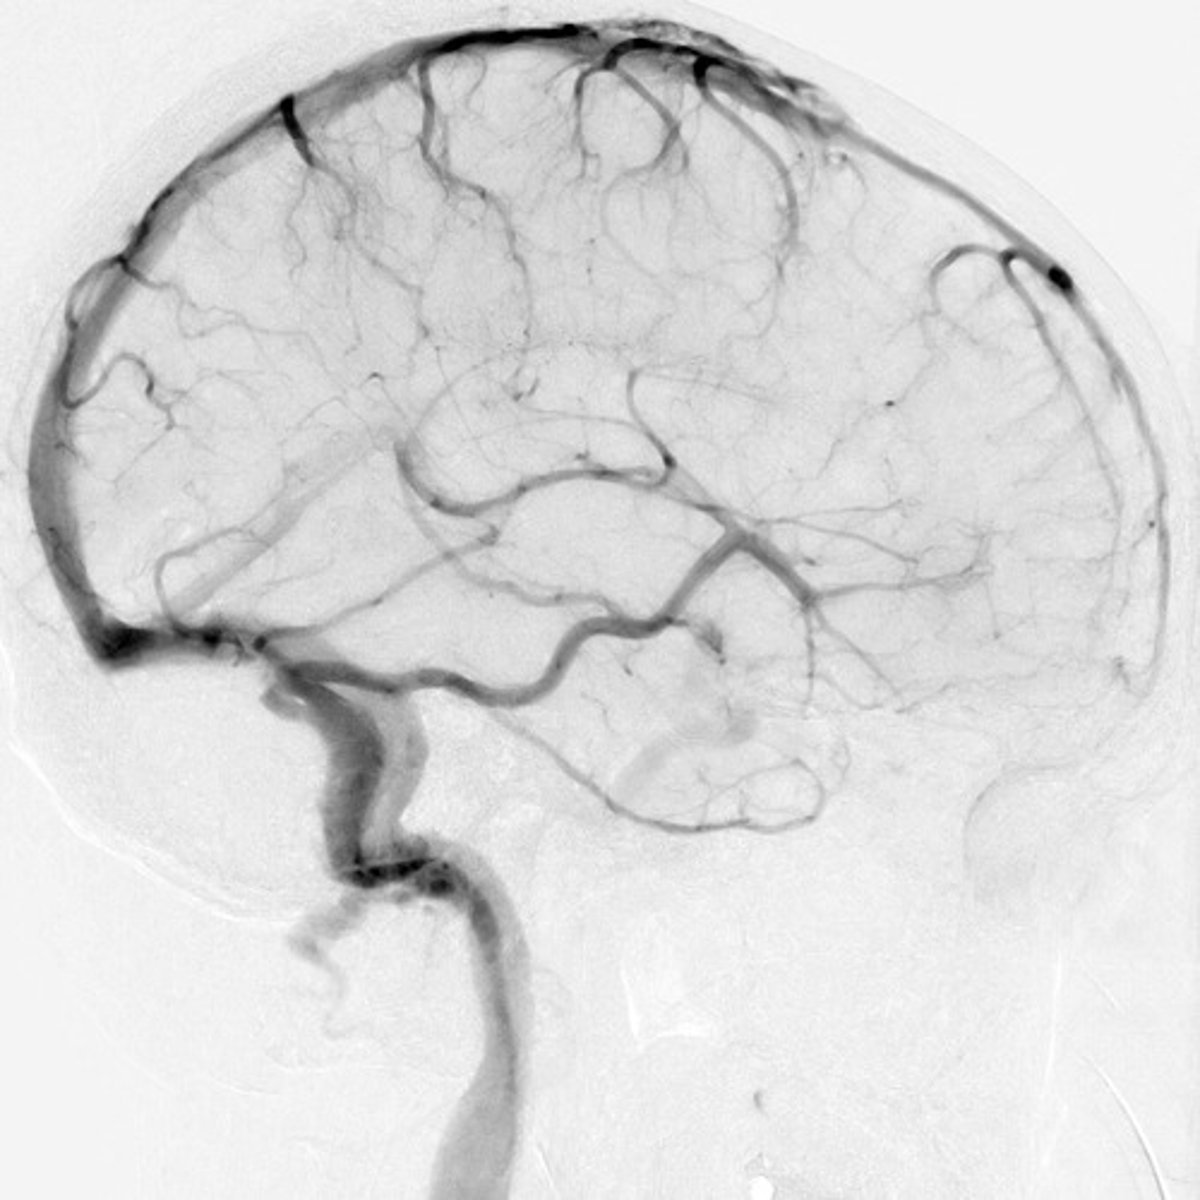

angiography

procedure that records a radiographic image of the inside of a blood vessel after injection of a contrast medium

coronary angiography

specialized type of angiography that helps diagnose stenosis or obstruction of the arteries that supply blood to the heart muscle